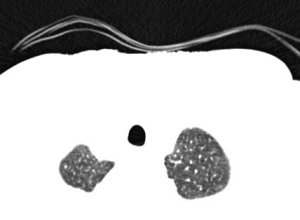

CT scan data is an important aspect of COPHIT. It provides a framework with which to perform patient specific treatment. Move the mouse over the patient to select a CT slice. Click on the body to highlight the segmented airways. Click here to view all CT scans for this patient.

Not all lungs are the same and COPHIT offers you the opportunity to design a drug delivery regime optimised for a particular lung condition. Optimised drug delivery for particular disease classes is possible with the use of the ‘lung library’ provided within the COPHIT environment.